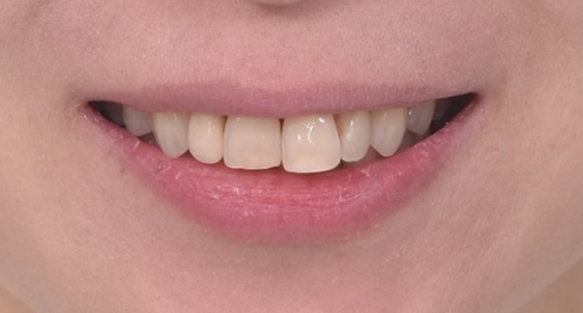

치료 마무리 후 모습입니다.

앞니가 깊게 물리는 과개교합이 개선이 되었습니다.

치간삭제로 블랙트라이앵글 사이즈를 줄일 수는 있지만 치간삭제가 과도하면 안되어서 소량의 블랙트라이앵글은 남았습니다.

치료 전 후 보겠습니다.

좌 - 치료 전 / 우 - 치료 후

치간삭제를 통한 앞니 돌출감 개선